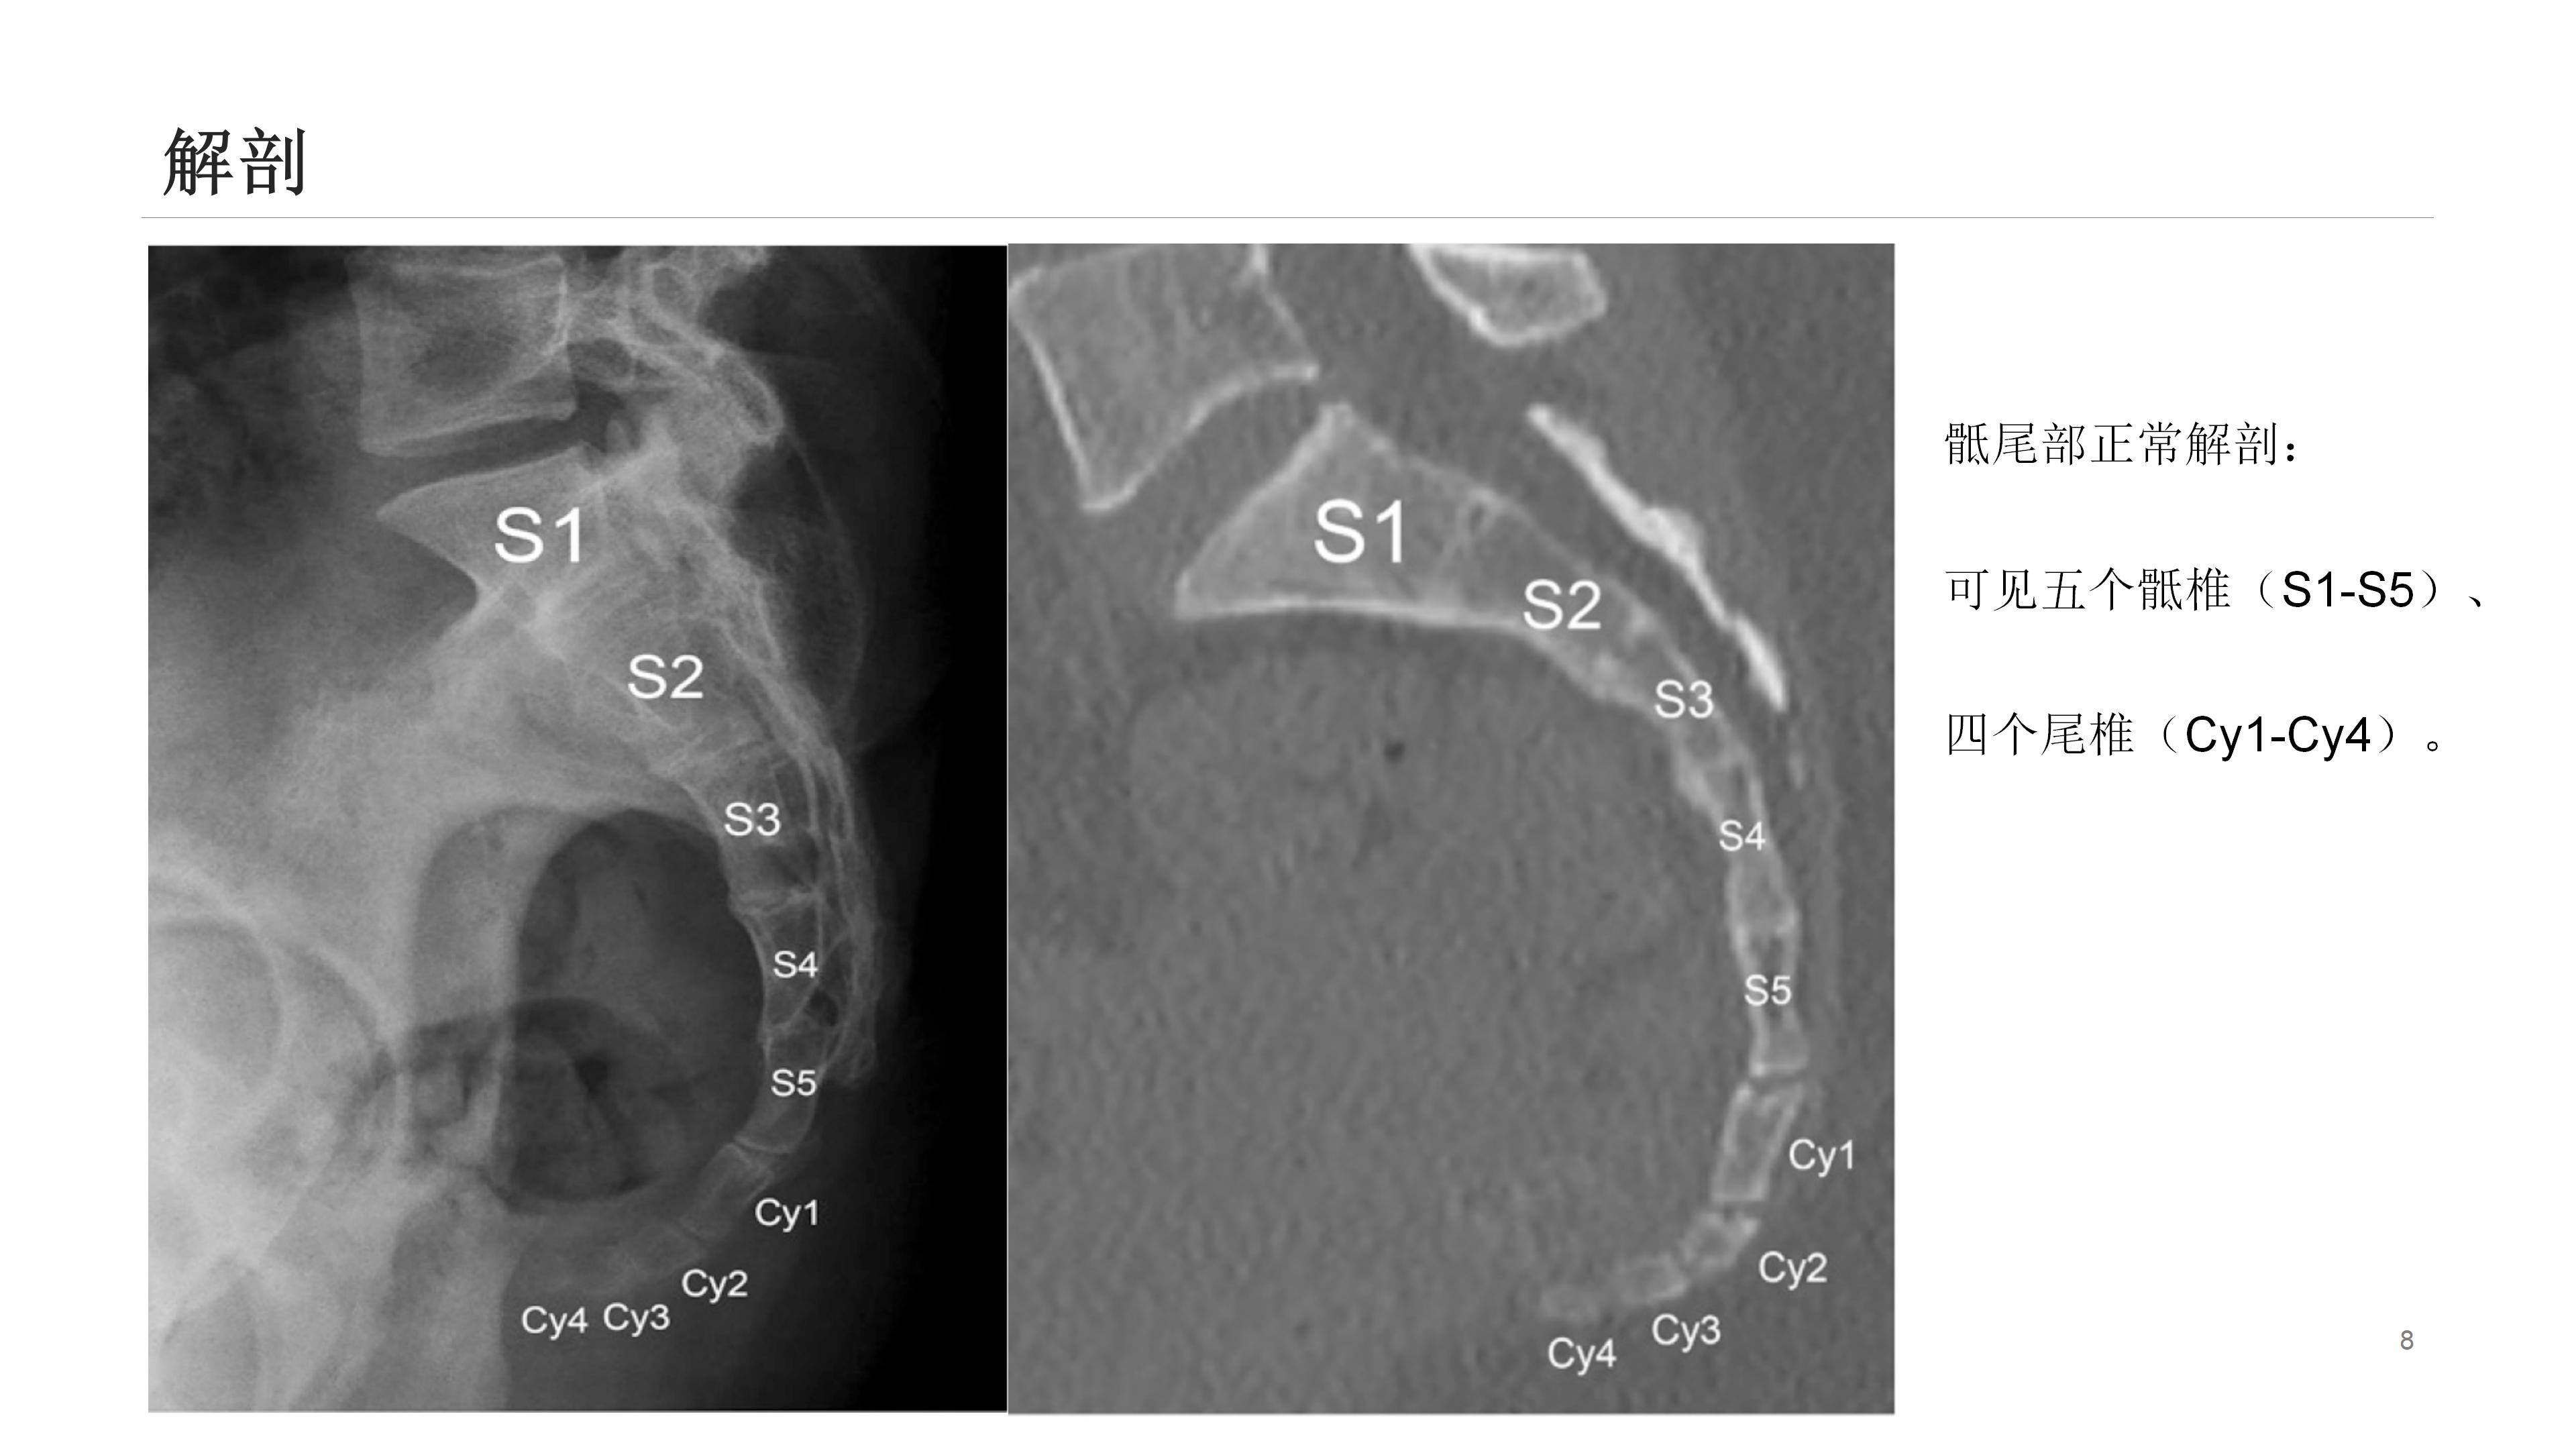

尾骨区域解剖结构复杂,众多结构皆可能引发该区域疼痛。影像学能出色呈现其解剖学特点,辨别受累结构可指导临床处置。尾骨疼痛乃常见临床症状,却难以评估和治疗。

通常,尾骨疼痛多在创伤后出现,初始静态平片检查可能正常,而动态平片(站立位及坐侧位平片)或可观察到异常尾骨移动,以此解释疼痛来源。